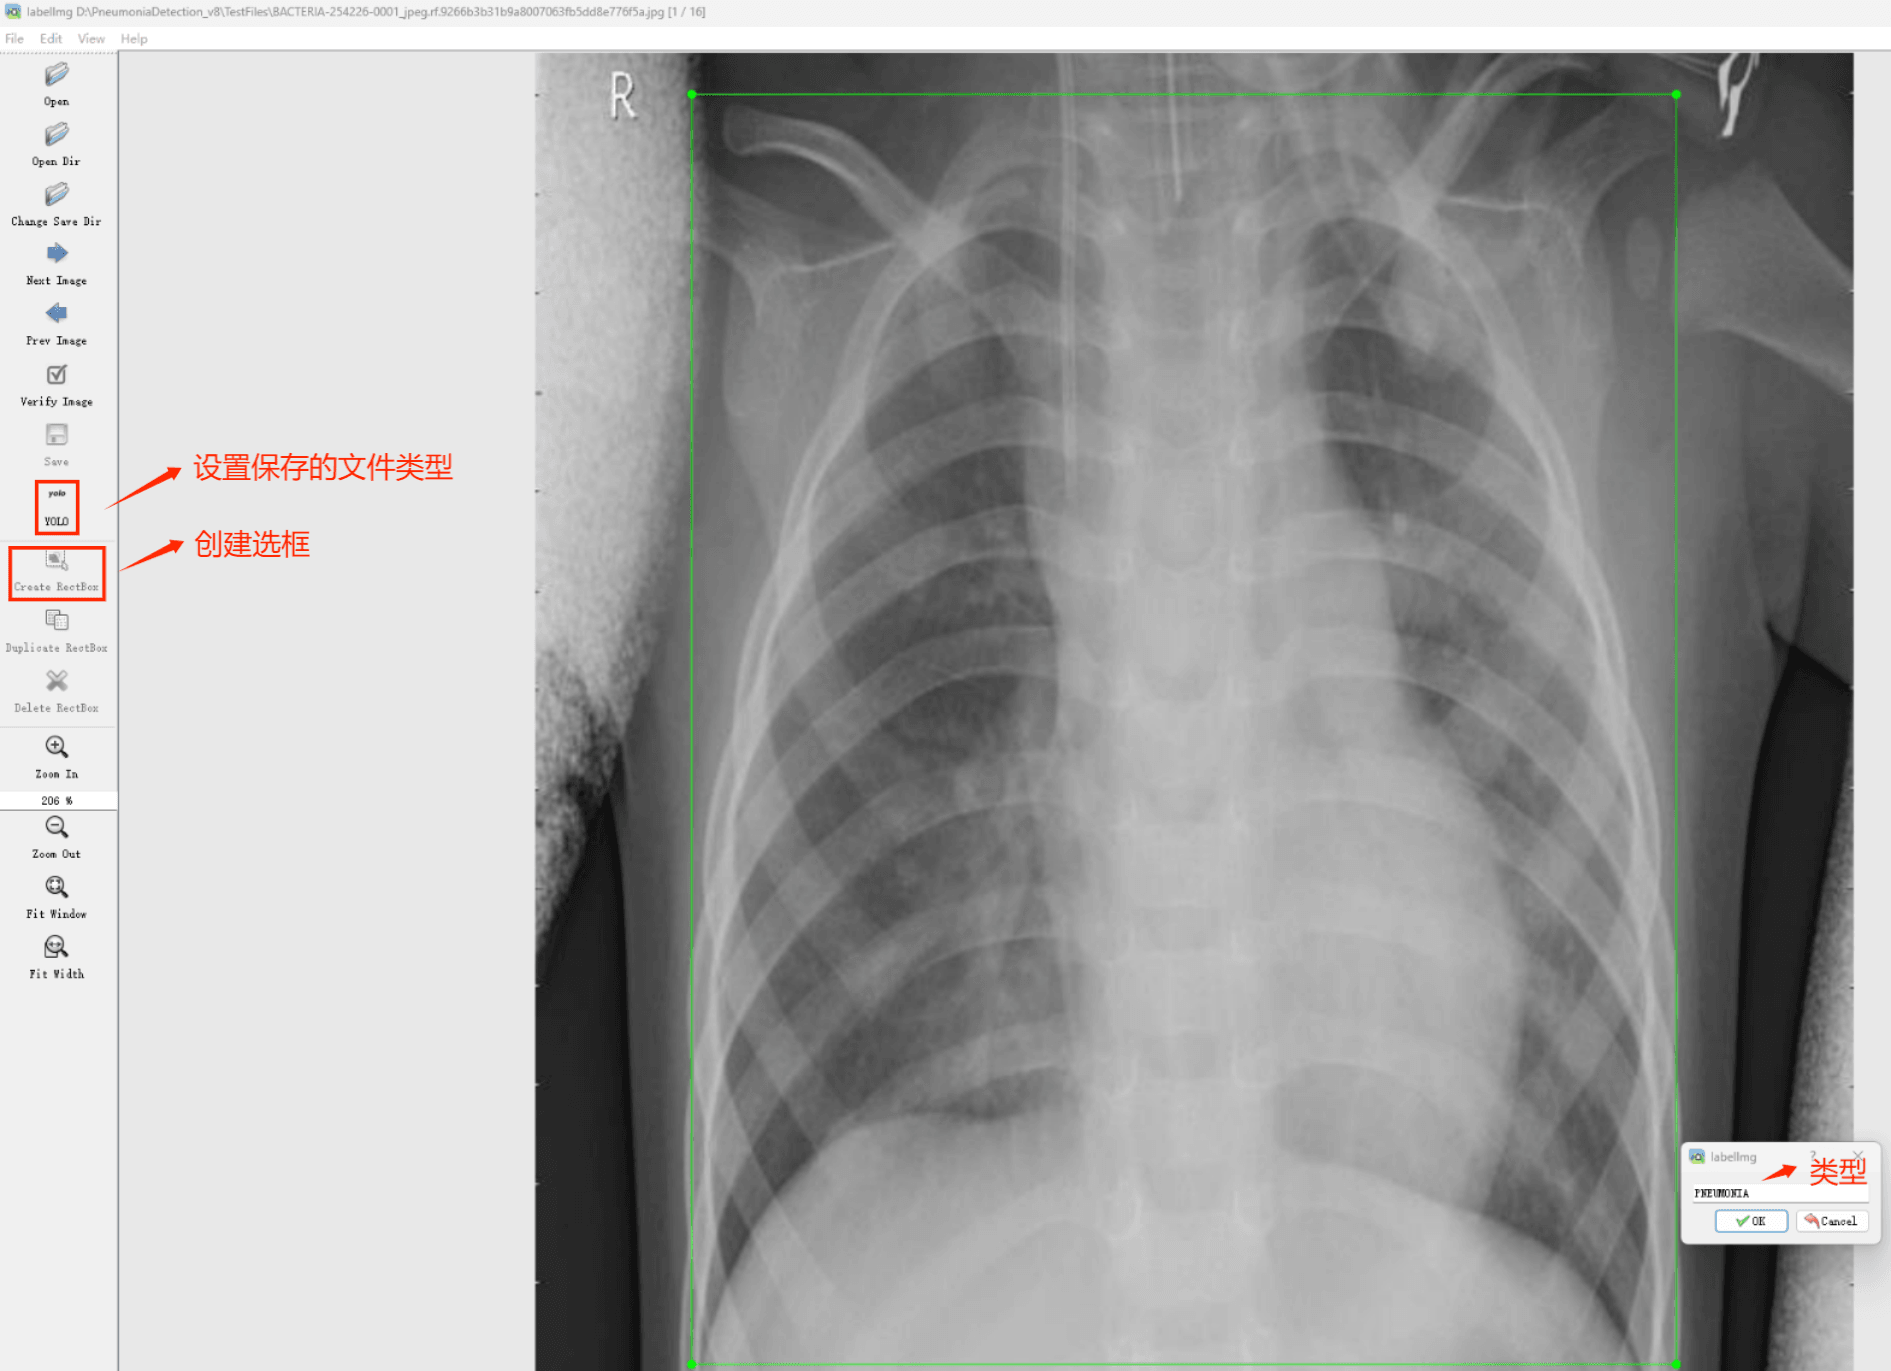

Tipps:为了收集各种肺炎相关图像的数据集,并借助Labelimg标注工具对每张图片进行标注;采用二分类检测技术将所有图片分为两类:一类是肺部正常影像,另一类是肺部炎症影像。

目标检测标注工具

(1)labelImg: 一款开源的图像标注工具软件, 其标签不仅适用于分类任务, 还特别适合目标检测. 安装该软件后, 操作者可以通过简单的图形界面进行标注操作. 软件采用Python编写, 并基于Qt框架构建图形界面, 使用起来非常直观方便. 虽然软件是英文界面, 但其注释文件采用PASCAL VOC格式存储为XML文件, 这种格式与ImageNet所采用的形式一致. 此外, labelImg还支持COCO数据集格式.

初识labelimg

打开后,我们自己设置一下

在View中勾选Auto Save mode

接下来我们打开需要标注的图片文件夹

请根据上图中的指示进行以下操作:

- 设置好标注文件存储路径

- 开始进行图像注解工作

- 使用矩形框选择目标区域

- 对选定的目标添加相应的标签

- 按住快捷键"d"切换至下一幅图片

- 重复上述步骤直到所有图片完成注解